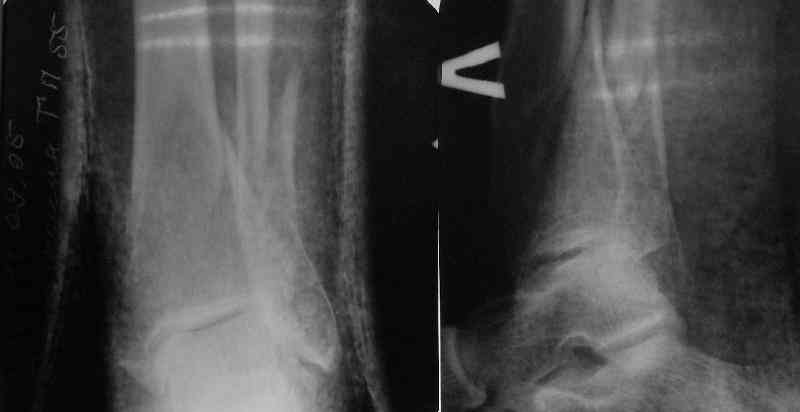

TDVC> little distal varus with some fibula distraction?

At least both the ankle mortise and tibial alignment look acceptable, don't they?

I am just trying to illustrate that prevention of 1)tibial valgus and 2)loss of reduction can be provided without fibular plating. Small changes of conventional nailing techniques allow to maintain reduction of the tibia reliably without adjunctive fibular stabilization.

In delayed cases acute length restoration performed only in the tibia may leave the fibula shortened thus change the mortise. So it is reasonable to restore length of both bones simultaneously by distractor and fix the fibula not with open reduction and plating but just by a single perQ screw. Example attached.